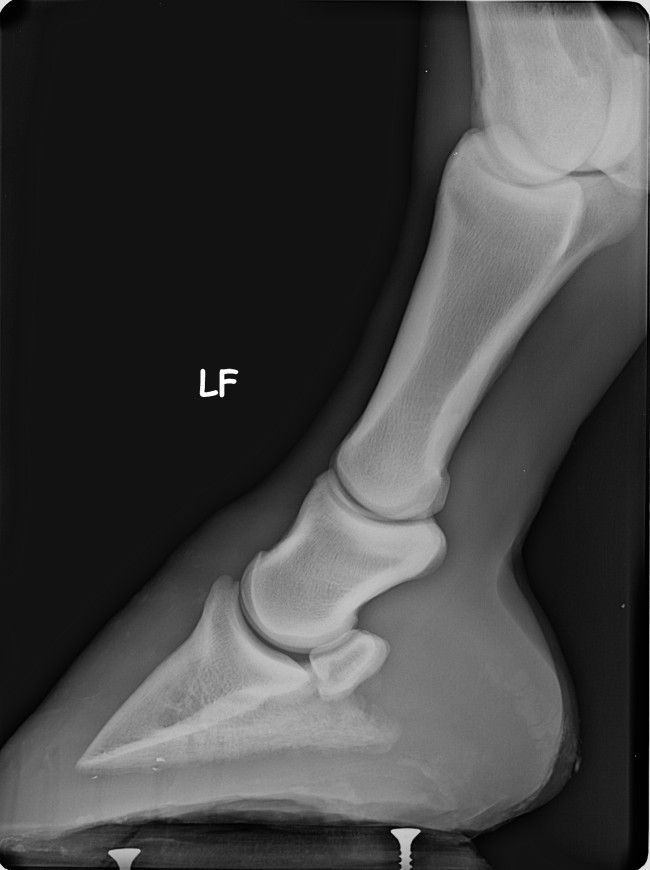

| Dire merci | les premières radios sont de juillet 2012 Voici les radios de l'antérieur droit fin septembre 2012 ![]() et celles de l'antérieur gauche ![]() ![]() |

| Dire merci | Merci je comprends mieux, alors au vu des radios le mien est atteint d'ostéite ? Et un cheval atteint d'ostéite peut il être remonté ? Le mien à la sole fine et la talon trop bas, on lu ia mis des fer à l'enver et là j'ai rajouté recement une plaque en cuir très amortissante. Dans l'espoir de le soulagé. Quand on a découvert la maladie, on m'a prescrit des anti inflammatoire pendant une semaine. Mais là j'ai l'impression qu'i les remet en positio nd soulagement... donc il faudrait que je lu redonne de l'anti inflammatoire ? |

Déconnecté | ben oui en voyant les radios, je me suis dit ostéïte direct. d'ailleurs elles sont assez impressionnantes. l'ostéïte a un caractère assez definitif,l'os ne peux pas se reminéraliser. les anti inflammatoires, c'est pour eviter qu'il y a ai une nouvelle infection qui déminéralise encore plus. quant à le remonter ....vu tes radios ... il faut imaginer que ses phalanges sont devenues aussi légère que de la roche volcanique pleine de trous ... au moindre choc, il va souffrir, et il risque des fissures de fatigue et de traumatisme aussi ... franchement, tes radios sont pas très encourageantes :S |

| Dire merci | j'ai eu le spécialiste au telephone... Alors mon cheval sera remontable sans problème par la suite. La je dois lui refaire une écho du pied, j'ai téléphoné au spécialiste B... Et m'envoie à dijon, j'attends de savoir si ils peuvent me faire l'échos. Le cheval n'avait pas qu'une ostéite mais aussi un soucis au tendon du à l'abaissement des talons suite au parage naturel... Donc avec l'échos, on va voir si c'est l'os ou el tendon le plus touché. Si c'ets l'os on fera une injection de tildren si c'est le ligament, j'aurai un autre produit. |